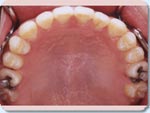

上顎(うわあご)は幅が狭く、前歯にでこぼこがあり、犬歯は外に飛び出していました。(A1, A2)

下顎の歯にもでこぼこがあり、幅の狭い上顎にあわせて内側に倒れていました。(A1, A3)

上顎を広げる治療を行い、それに合わせて下の歯もまっすぐにしました。